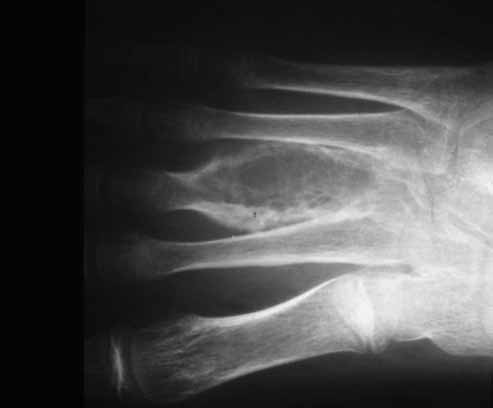

Fig 1.- Radiografía simple del pie derecho. Lesión metafisio-diafisaria del tercer metatarso bien delimitada con trabeculación fina en su interior, adelgazamiento cortical y ausencia de esclerosis y de reacción periostal. |